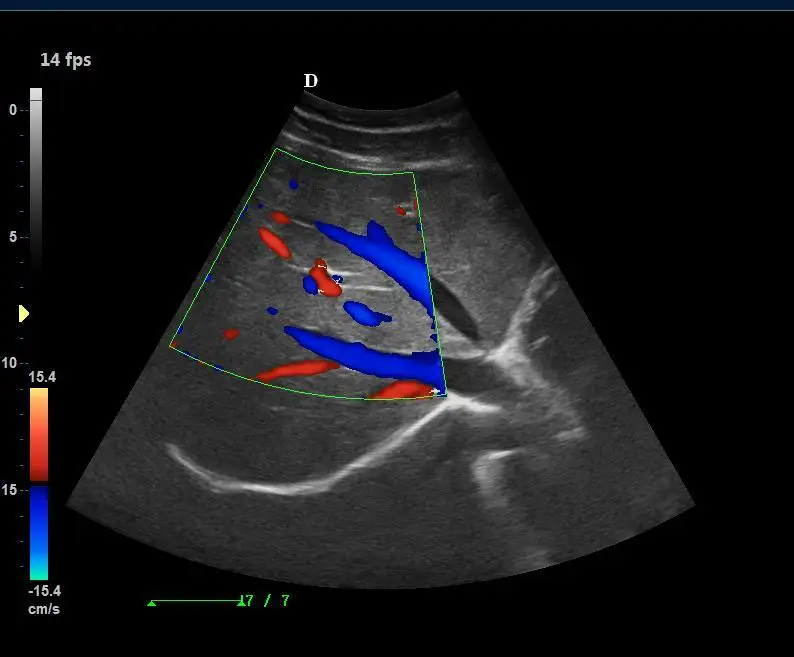

Operating Mode | B, 2B, 4B, B/M, M, B/C/D, B/D, CW, PW, velocity, power(direction), histogram, triples/duplex etc. |

Standard Configuration | Main Unit 3.5Mhz convex probe 4D Volume probe and software 19'LED display with 10.4’ touch screen CW function ( work with phased array probe) USB ports, DICOM 3.0,DVD-RW |